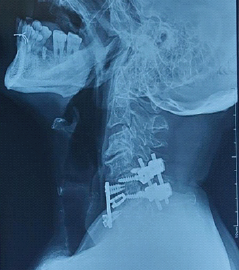

A Rare Case of C5–C6 Bilateral Facetal Dislocation with Central Cord Syndrome Managed by Staged Stabilization

Soumyamay Mukherjee , K Pradeep Pandian , Vishnu Senthil